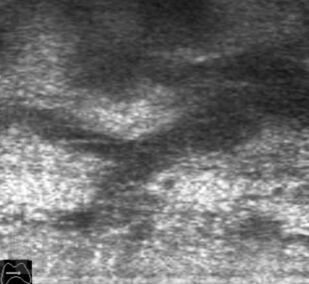

В основу монографии положены материалы собственных исследований и практический опыт использования ультразвуковых методов диагностики при обследовании пациентов после хирургических вмешательств на щитовидной железе. Продемонстрированы диагностические возможности ультразвукового исследования в оценке состояния оперированной щитовидной железы в раннем и отдаленном послеоперационном периоде. Обобщена, систематизирована и представлена ультразвуковая семиотика зоны операции в ближайшие сроки после хирургических вмешательств и отражена динамика выявленных изменений. Убедительно показано, что ультразвуковое исследование может быть эффективным методом послеоперационного наблюдения.